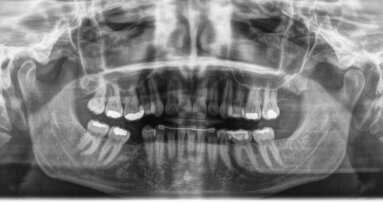

Tuttavia, il biofilm si forma su irregolarità quali micro-graffi, micro-fessure e rialzi della superficie degli allineatori. Con l’obiettivo finale di creare un farmaco efficace e sicuro per la distruzione dei biofilm, i ricercatori della Peoples’ Friendship University of Russia hanno isolato e analizzato la composizione di questo biofilm e la capacità dei microrganismi di formarlo, determinandone gli indicatori morfometrici e densitometrici.

I microrganismi più dominanti sugli allineatori, dopo averlo indossato per un solo giorno, erano i Bifidobatteri, Escherichia coli, Peptostreptococcus anaerobius, Porphyromonas gingivalis, Prevotella buccae, Staphylococcus aureus e Streptococcus mitis. I ricercatori sono stati anche in grado di identificare i microrganismi che sviluppano maggiormente il biofilm e che quindi esercitano un’influenza predominante.

A causa del rischio di ridotta efficacia della terapia antinfiammatoria e dello sviluppo di carie e altre malattie infiammatorie, la formazione di biofilm durante la terapia ortodontica richiede un monitoraggio costante. Gli scienziati si sono quindi concentrati sull’interazione tra gli allineatori e la microflora orale, in particolare per quanto riguarda la composizione delle specie e la resistenza agli antibiotici. I microrganismi orali e le loro proprietà, come la formazione di biofilm, l’adesione e la capacità di incorporare particelle solide, cambiano nel tempo, a seconda del luogo e di determinate condizioni. Le ricerche citate dai ricercatori hanno pertanto suggerito la necessità di studi a più lungo termine per valutare se i livelli e la varietà della microflora presenti in bocca con l’uso di apparecchi ortodontici ritornino ai livelli precedenti la terapia.